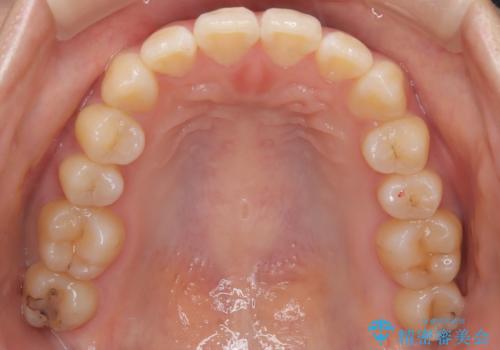

- 患者様は、右下第2小臼歯(5番)の先天欠如により乳歯が残存している状態でした。

加えて、**下顎前歯部に叢生(歯のがたつき)**が見られ、審美的・機能的な改善を希望されて来院されました。

下顎前歯の叢生も同時に改善できるよう、全体的なワイヤー矯正による治療計画を立案しました。

下顎前歯の叢生が整い、右下5番部には機能的かつ審美的なインプラント補綴が完了しました。